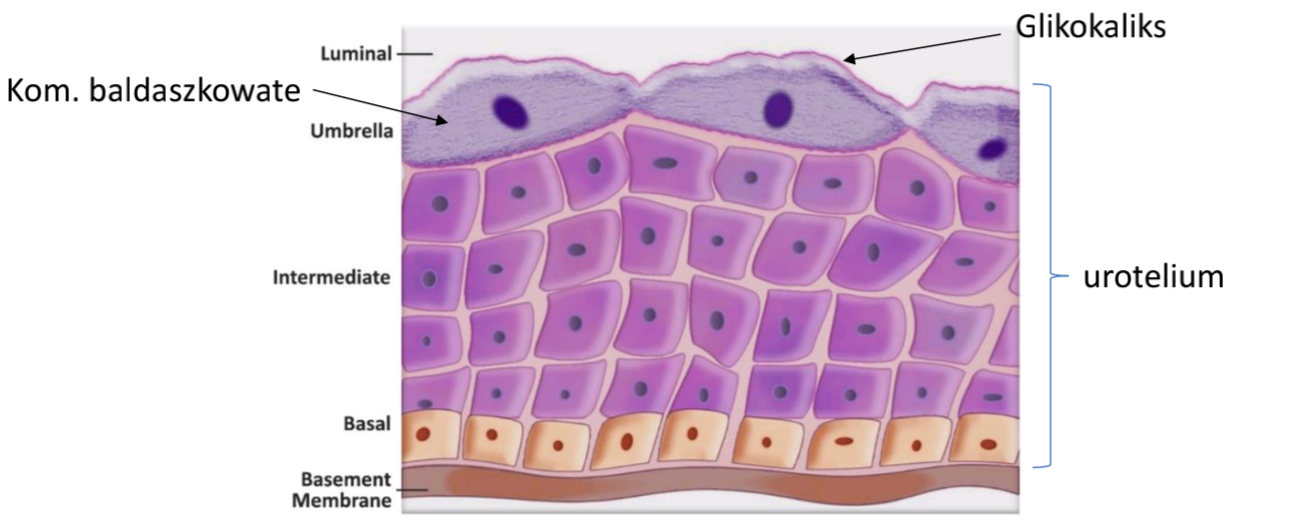

Nabłonek przejściowy, inaczej nazywany urotelium

Gdzie?- Występuje w większej części dróg moczowych: kielichy nerkowe, moczowody, pęcherz moczowy, początkowy odcinek cewki moczowej.

Czym jest urotelium?

Na powierzchni tego nabłonka (wyściełanie światła dróg moczowych) znajdują się komórki baldaszkowate, zwane także parasolowatymi (ang. umbrella cells). Jak szerokie baldachimy, albo parasole, pokrywają mniejsze głębiej położone pozostałe komórki nabłonka. Komórki baldaszkowe tworzą barierę dla toksyn znajdujących się w moczu (pokryte są glikokaliksem i specyficznymi białkami barierowymi jak uroplakiny)oraz mają zdolność silnego rozciągania się (ważne dla wypełniania się pęcherza moczem).